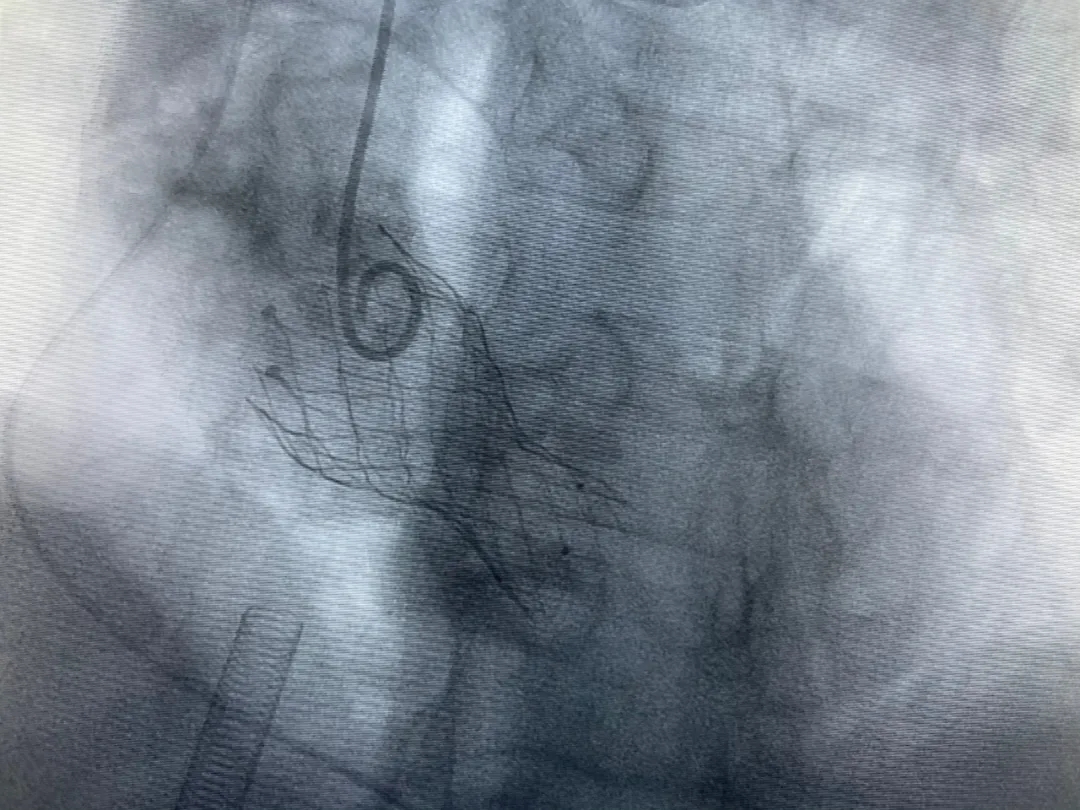

結(jié)合老人病情特點(diǎn):年齡高、室壁厚、左室腔小、瓣膜鈣化嚴(yán)重,術(shù)中球囊擴(kuò)張和瓣膜釋放過(guò)程有循環(huán)崩潰可能;為降低此種風(fēng)險(xiǎn)、最大程度提高手術(shù)成功率,張金洲副院長(zhǎng)在術(shù)前組織了由楊金保博士帶領(lǐng)的TAVR團(tuán)隊(duì)多次反復(fù)溝通、討論,制定了各種應(yīng)急處理方案。最終經(jīng)過(guò)TAVR團(tuán)隊(duì)的默契配合,手術(shù)歷時(shí)2小時(shí),用20#球囊預(yù)擴(kuò)張后順利植入23#主動(dòng)脈瓣生物瓣膜,再次后擴(kuò)后主動(dòng)脈根部造影顯示:人工主動(dòng)脈瓣生物瓣位置良好,瓣葉開(kāi)閉正常;冠脈顯影良好。經(jīng)食道超聲顯示:主動(dòng)脈瓣葉活動(dòng)度良好,主動(dòng)脈跨瓣壓差約35mmHg,未見(jiàn)瓣周漏及明顯返流。出手術(shù)室前老人便已蘇醒,自訴憋悶癥狀完全消失。